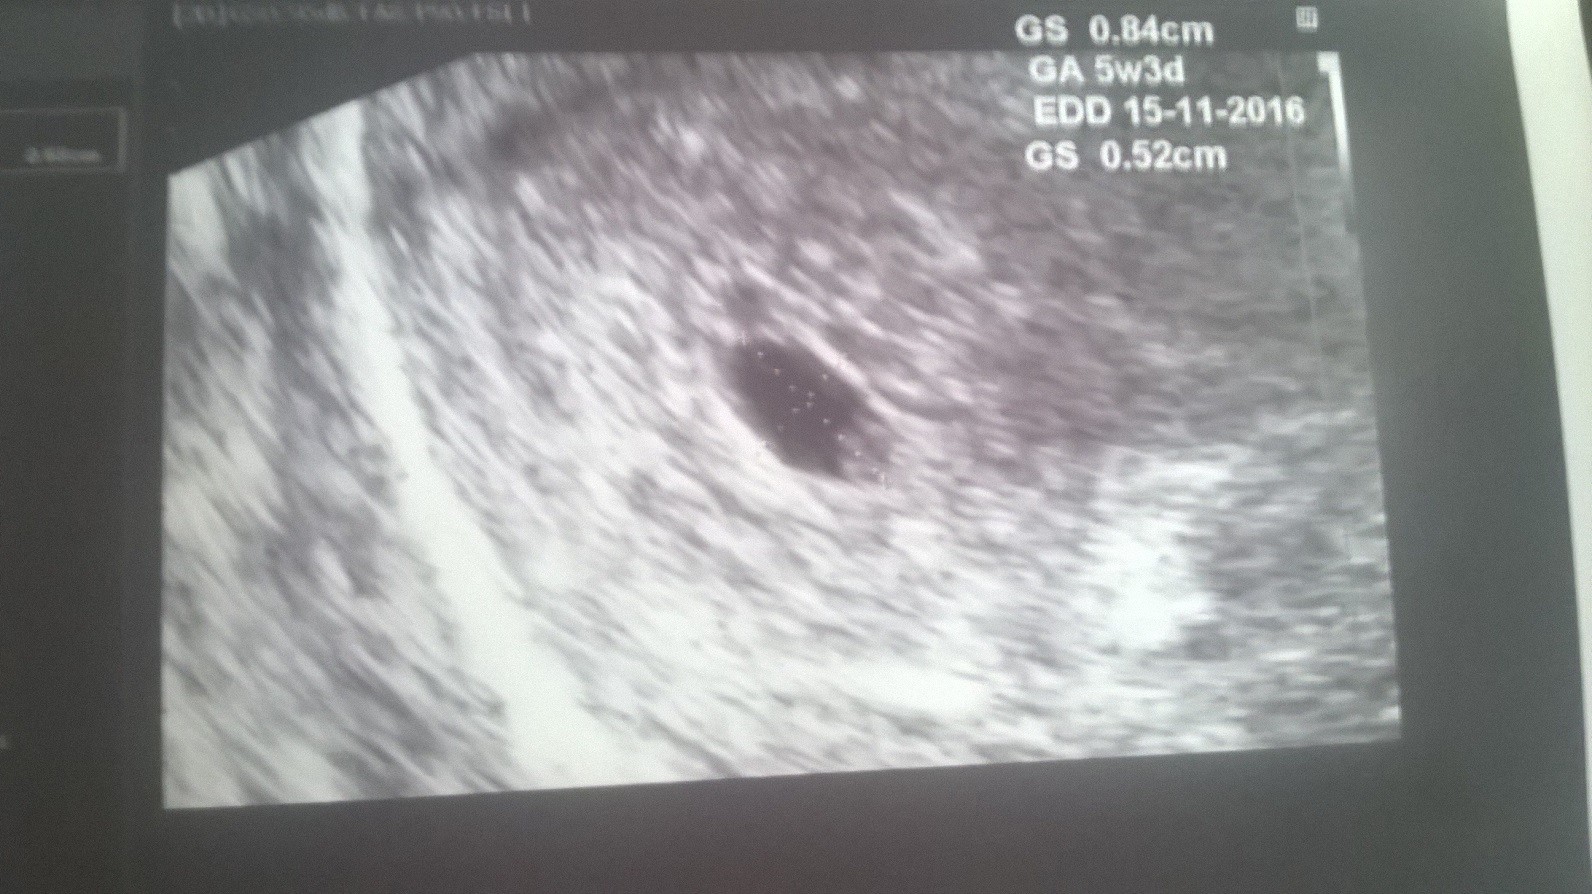

Patrząc na pomiary to faktycznie wydaje się, że coś jest nie tak, ale zobacz jak kiepski jest obraz na tych pierwszych dwóch. Tam milimetr w tą czy w drugą już robi różnicę. A co do wymiarów to nie brałabym pod uwagę tych robionych przez twoją byłą gin, bo po prostu się nie przykładała. Tak na prawdę po prostu trzeba czekać na rozwój sytuacji i wierzyć, że będzie dobrze.